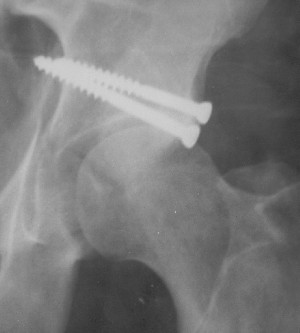

Послеоперационный снимок прямой 5/05/03

Послеоперационный снимок боковой 5/06/03

Больной 18 мая 2003 года в автоаварии получил перелом левой вертлужной впадины, вывих бедра. Госпитализирован в один из стационаров области.Вывих вправлен. В последствии бедро вывихивалось еще дважды. На консультацию был представлен снимок от 19.05.03г., больной переведен к нам 3.06.03г. Снимок при поступлении - перелом впадины, задне-верхний вывих бедра. 05.06.2003 г. выполнено открытое вправление вывиха левого бедра и остеосинтез стенки вертлужной впадины двумя винтами. Послеоперационный период без осложнений. Объем движений в левом тазобедренном суставе восстановился полностью. Выписан на амбулаторное лечение в удовлетворительном состоянии с рекомендациями 3 месяца ходить на костылях без нагрузки на оперированную конечность. На контрольных рентгенограммах левого тазобедренного сустава 13.10.2003 г. - признаки консолидации перелома; плотность, форма головки и состояние суставных поверхностей удовлетворительные. Разрешена дозированная осевая нагрузка, на конечность с использованием дополнительной опоры. 19.12.2003 г. больной обратился с жалобами на боли в левом тазобедренном суставе. На рентгенограммах левого тазобедренного сустава 19.12.2003 г., 20.02.04г. - асептичекий некроз головки бедра. 5.04.04г. - эндопротез. Сейчас ходит без трости, не хромает. Особенность эндопротезирования - при удалении винтов прослежена линия перелома заднего края впадины и предложено установить чашку несколько меньшего диаметра, чтобы она была покрыта несломанной частью.